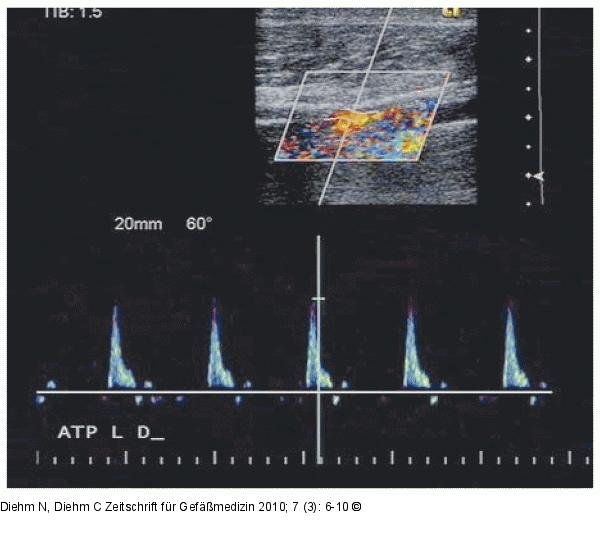

Abbildung 5: A. tibialis posterior

Duplexsonographische Darstellung der distalen A. tibialis posterior, welche nach 9 Monaten frei von Restenosen ist. Die klinische Präsentation ist weiterhin bland und der Patient hat keine Beschwerden. |